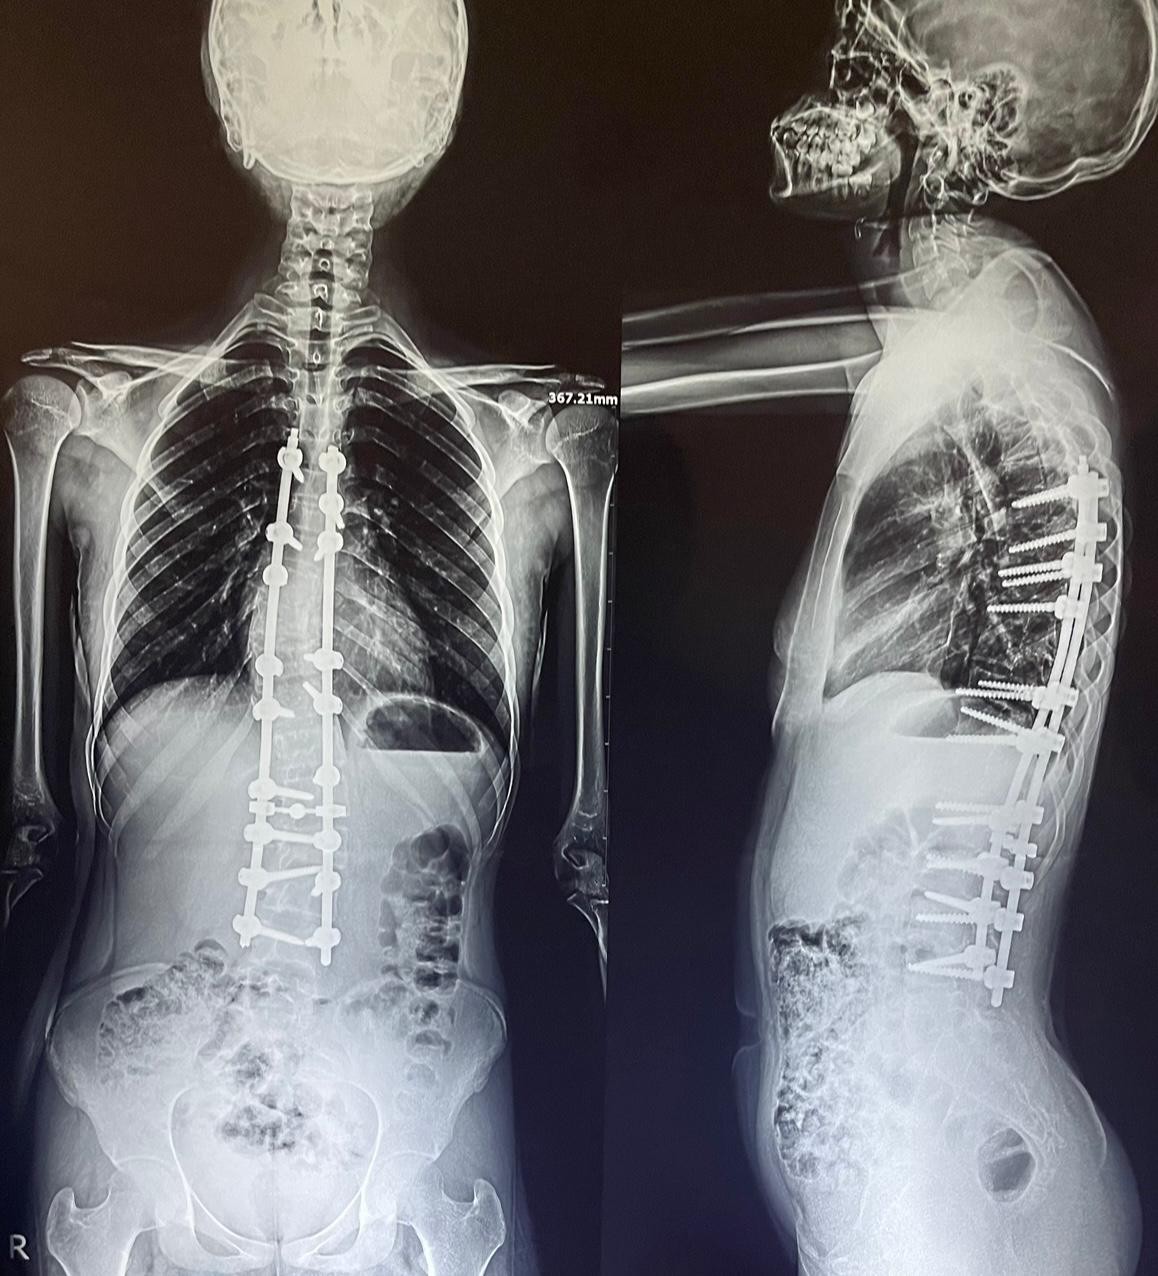

double curvature of the thoracic and lumbar vertebrae

An advanced corrective surgery was performed to treat double curvature in thoracic and lumbar vertebrae. This condition involves abnormal curvatures in both the chest and lower back areas of the spine, affecting posture, movement, and causing chronic pain.

- Correcting double curvatures in thoracic and lumbar vertebrae

- Restoring balance and alignment to the spine

- Use of advanced internal fixation system